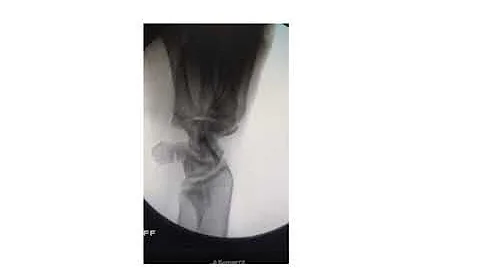

2.5 Captivate Screw Scaphoid Fracture